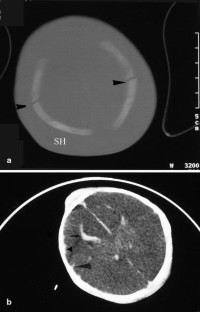

The purpose of this paper is to describe brain pathology in neonates after major traffic trauma in utero during the third trimester. Our patient cohort consisted of four neonates born by emergency cesarean section after car accident in the third trimester of pregnancy. The median gestational age (n=4) was 36 weeks (range: 30–38). Immediate post-natal and follow-up brain imaging consisted of cranial ultrasound (n=4), computed tomography (CT) (n=1) and post-mortem magnetic resonance imaging (MRI) (n=1). Pathology findings were correlated with the imaging findings (n=3). Cranial ultrasound demonstrated a huge subarachnoidal hemorrhage (n=1), subdural hematoma (n=1), brain edema with inversion of the diastolic flow (n=1) and severe ischemic changes (n=1). In one case, CT demonstrated the presence and extension of the subarachnoidal hemorrhage, a parietal fracture and a limited intraventricular hemorrhage. Cerebellar hemorrhage and a small cerebral frontal contusion were seen on post-mortem MRI in a child with a major subarachnoidal hemorrhage on ultrasound. None of these four children survived (three children died within 2 days and one child died after 1 month). Blunt abdominal trauma during pregnancy can cause fetal cranial injury. In our cases, skull fracture, intracranial hemorrhage and hypoxic-ischemic encephalopathy were encountered.